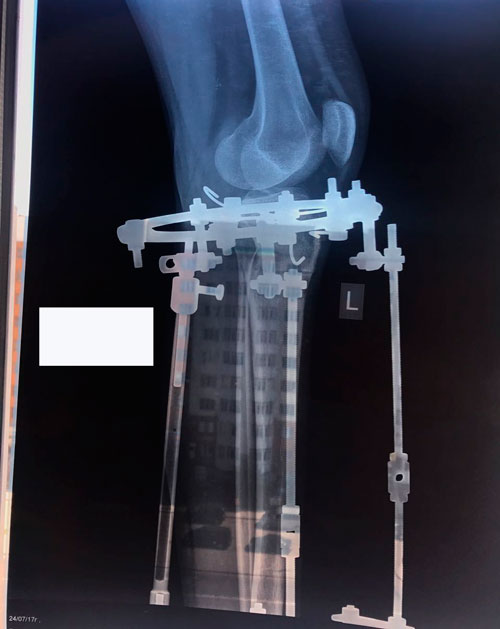

Исходник - 19 лет.

Дата операции 25.05.2017г.

В процессе круток

58 дней.

Через 2 недели можно на снятие аппаратов.

Дата снятия аппаратов 10.08.2017г.

Срок лечения 75 дней.